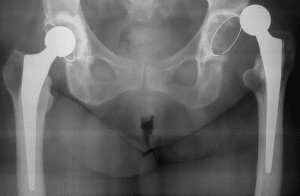

Вывих эндопротеза тазобедренного сустава Вывих бедра — редкая и неприятная патология, возникающая по разным причинам. Лечение в этом случае может быть консервативным или хирургическим. Все зависит от характера вывиха и самочувствия пациента. Вывих эндопротеза: причины По статистике вывих эндопротеза чаще диагностируется у представителей женского пола, чем у представителей мужского пола. В группу риска также входят …